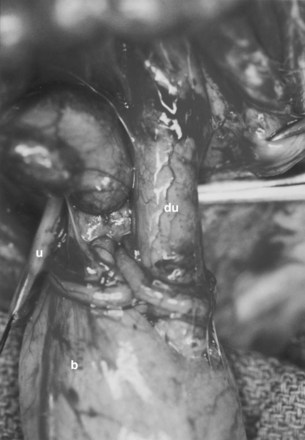

A system of progressive dilation for ureters and bladders has been proposed but has not been attempted clinically (Lailas et al, 1996; Satar et al, 1999). In an animal experiment, rabbits underwent unilateral ureteral ligation at the ureterovesical junction. A catheter was threaded into the proximal ipsilateral ureter and connected to an injection port that was secured subcutaneously. A saline-antibiotic solution was injected daily subcutaneously into the injection port. After 1 month of daily saline-antibiotic–solution injections, the ureteral units were dilated at least 10-fold, and the diameter exceeded that of adjacent colon in each instance (Fig. 19–7). Augmentation cystoplasty was performed with the reconfigured dilated ureteral segment, resulting in an increased bladder capacity ranging from 190% to 380% (Lailas et al, 1996). In a similar system, a dilating indwelling catheter was used to dilate ureteral tissue in pigs (Ikeguchi et al, 1998).

Figure 19–7 Progressive dilation can be performed in a normal-caliber ureter, which can be subsequently used for ureterocystoplasty. After placement of a ureteral dilation device, comparison is made of progressively dilated ureter (du) and native undilated ureter (u) coming off the bladder (b).